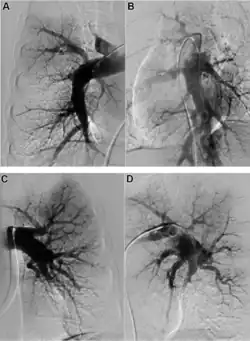

Early diagnosis remains a challenge in CTEPH, with a median time of 14 months between symptom onset and diagnosis in expert centres.[7] A suspicion of PH is often raised by echocardiography, but an invasive right heart catheterisation is required to confirm it.[6] Once PH is diagnosed, the presence of thromboembolic disease requires imaging. The recommended diagnostic algorithm stresses the importance of initial investigation using an echocardiogram and V/Q scan and confirmation with right heart catheter and pulmonary angiography (PA).[8]

Both V/Q scanning and modern multidetector CT angiography (CTPA) may be accurate methods for the detection of CTEPH, with excellent diagnostic efficacy in expert hands (sensitivity, specificity, and accuracy of 100%, 93.7%, and 96.5% for V/Q and 96.1%, 95.2%, and 95.6% for CTPA).[9] CTPA alone cannot exclude the disease, but may help identify pulmonary artery distension resulting in left main coronary artery compression, pulmonary parenchymal lesions (e.g. as complications from previous pulmonary infarctions), and bleeding from bronchial collateral arteries.[10]

Specialist imaging using either magnetic resonance or invasive PA is necessary to determine risks and benefits of interventional treatment with PEA or BPA.[8]